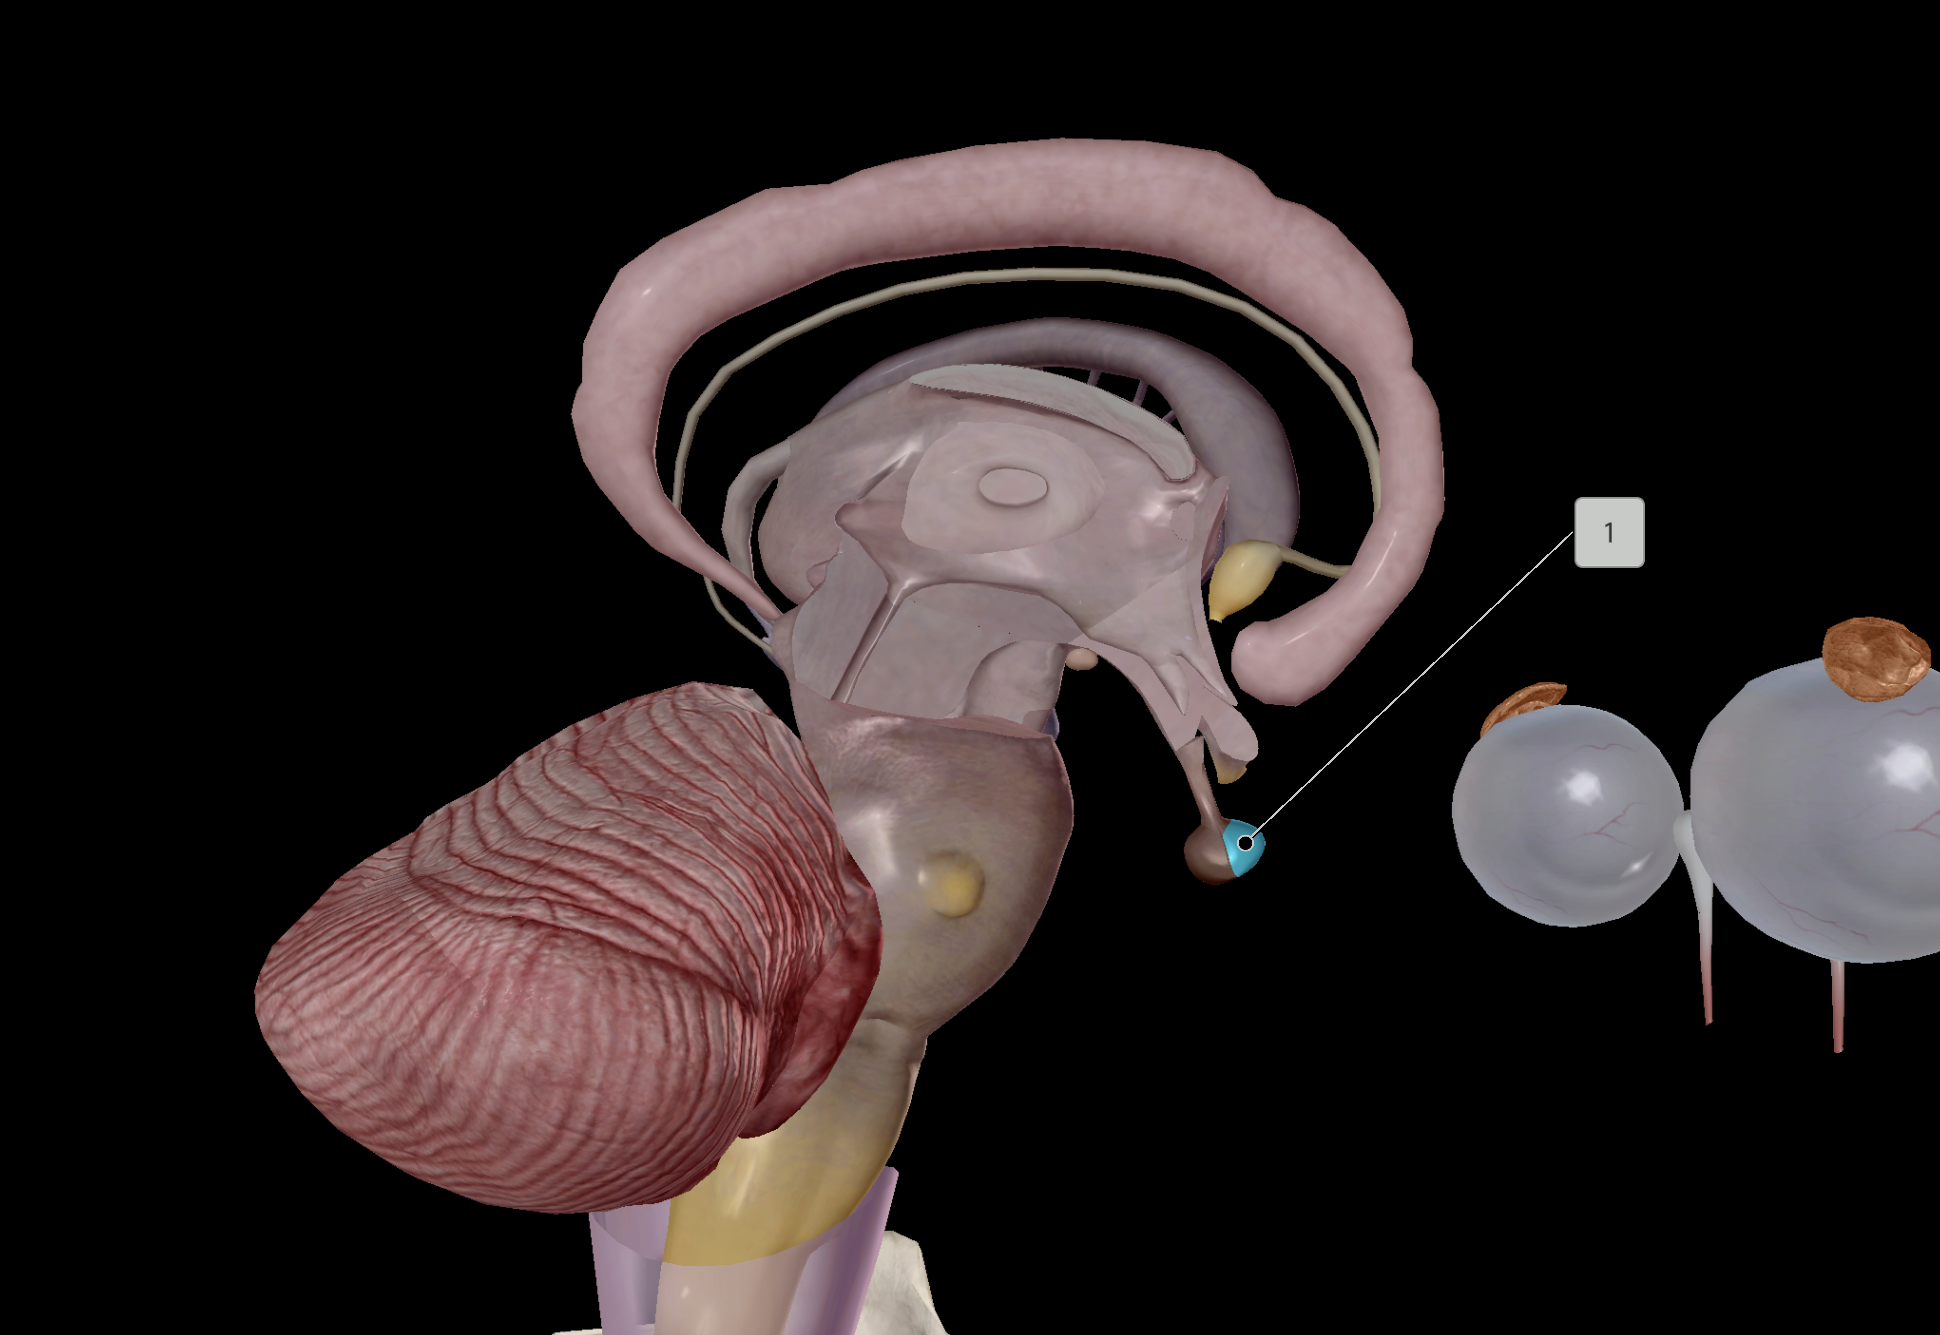

Hypothalamus